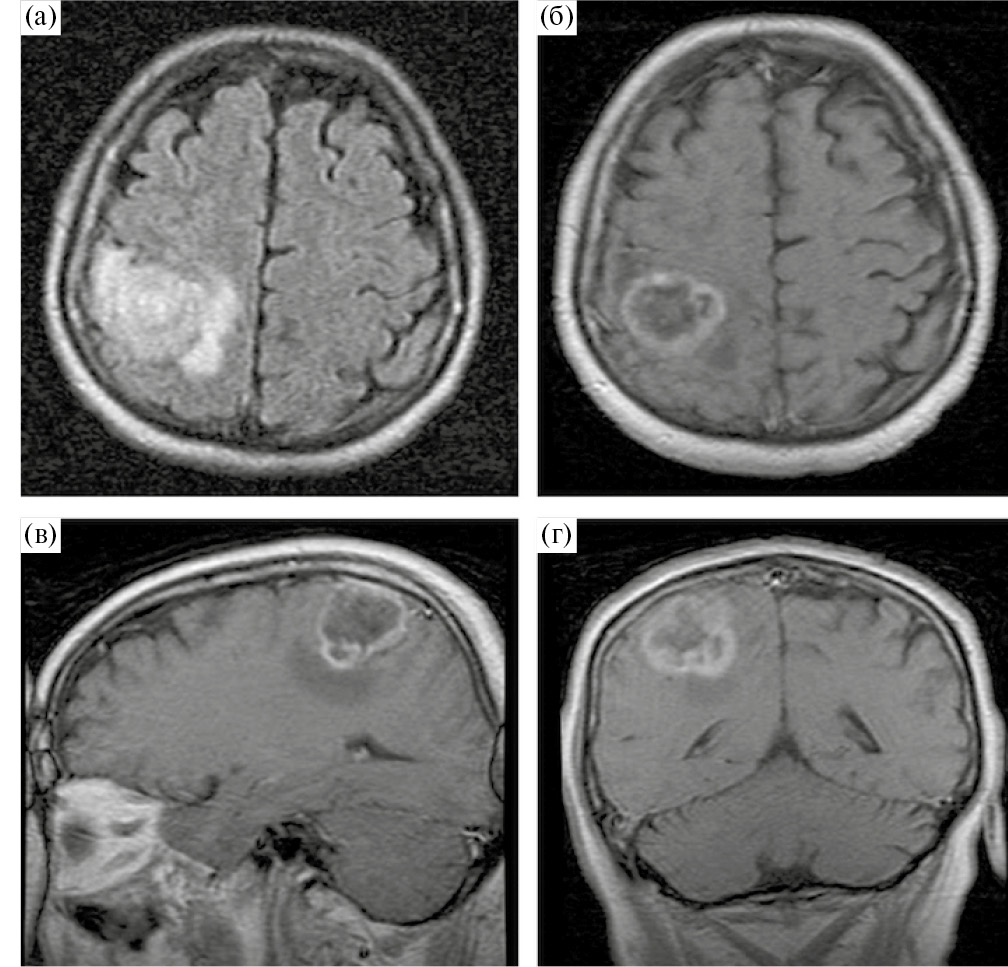

Учитывая локализацию процесса и клиническую картину заболевания, в качестве предоперационной подготовки пациенту были проведены фМРТ с визуализацией моторных зон и МР-трактография с построением КСТ (рис. 4).

Рис. 4. МРТ у пациента с внутримозговой опухолью правой теменной доли. (а, б) – данные фМРТ; (а) – оранжевым цветом обозначена корковая зона ноги, располагающаяся вовнутрь и на некотором отдалении от медиальной границы опухоли; (б) – представлена зона руки, прилегающая к переднему краю опухоли; (в, г) – данные МР-трактографии (CSD HARDI), использованный алгоритм построения позволил построить и разделить волокна КСТ, иннервирующие ногу (горчичный цвет), руку (фиолетовый), лицо (зеленый). Волокна КСТ прилегают к медиальному и переднему краям опухоли.

Fig. 4. fMRI (leg and arm areas) and MR-tractography (CSD HARDI, yellow – leg, purple – hand, green – facial muscles) before surgery.

В связи с непосредственной близостью опухоли к моторным центрам головного мозга запланировано проведение операции с обязательным нейрофизиологическим мониторингом, включающим динамику ТК МВП, прямую кортикальную и субкортикальную монои биполярную стимуляции и использование магнитной интраоперационной навигационной системы FIAGON. Для использования последней данные фМРТ, МР-трактографии и структурной МРТ были корегистрированы в едином файле. Для демаркации границ опухоли также использовалась флуоресцентная навигация (препарат «Аласенс»). Опухолевая ткань светилась ярко-розовым цветом.